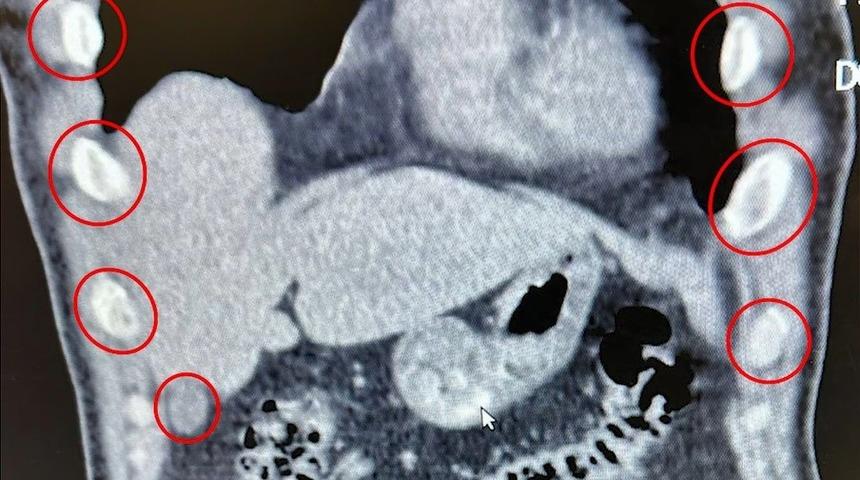

Şahısların yapılan tıbbi müdahalesinde, yuttukları 136 kapsül halinde toplam 1 kilo 48 gram metamfetamin ele geçirildi.